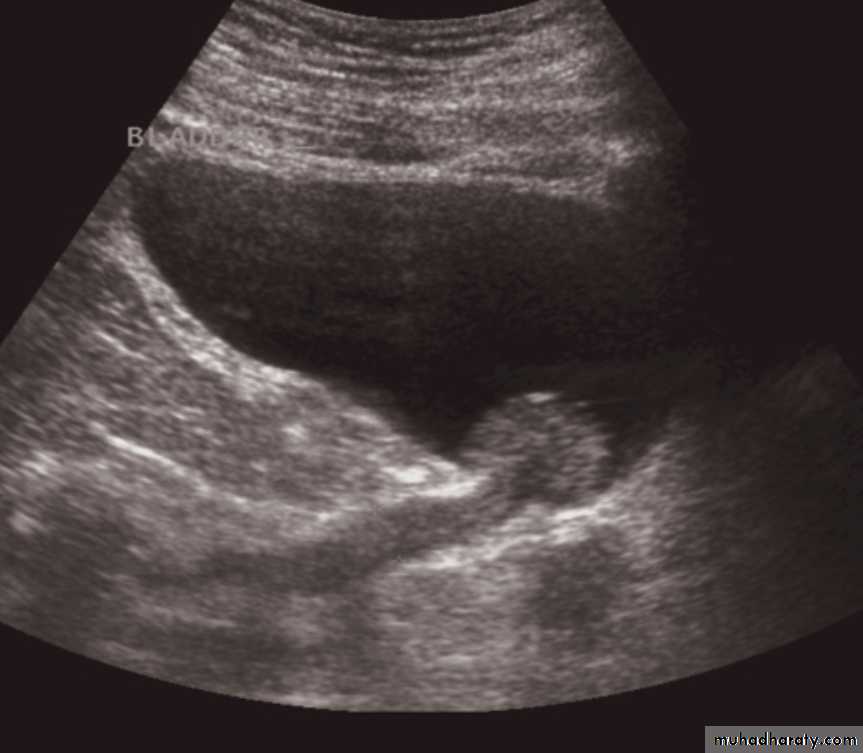

Simple cysts

Very common.

Filled with clear fluid(i.e anechoic).

Show obvious echoes from the front and back walls and posterior acoustic enhancement.

Most are spherical in shape.

Imperceptible walls

Solitary or multiple ,unilocular (simple)or have septations (not a simple cyst)

If contain low level echoes in dependent portion complicated by Hhg or infection.

No further investigations are needed.